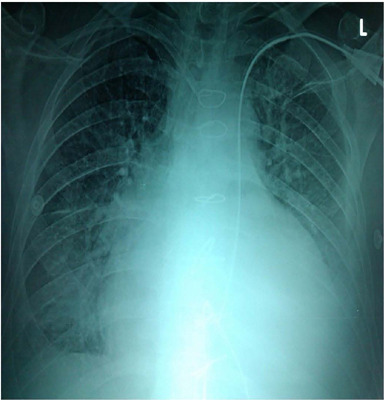

Persistent left superior vena cava (PLSVC) is a common congenital venous anomaly, usually associated with other congenital heart diseases (12%). Its incidence in the general population is 0.5%. In cardiac surgery patients, it is suspected when using the left subclavian vein or left internal jugular vein for central venous catheter or hemodialysis catheter placement. Transthoracic ultrasound exam is useful in confirming the position of catheters in the venous system by injecting a 5% glucose solution that can be visualized in the right atrium after administration through the catheter. Hemodialysis catheters can be inserted in the PLSVC with good catheter function and no major risk in increase of complications.